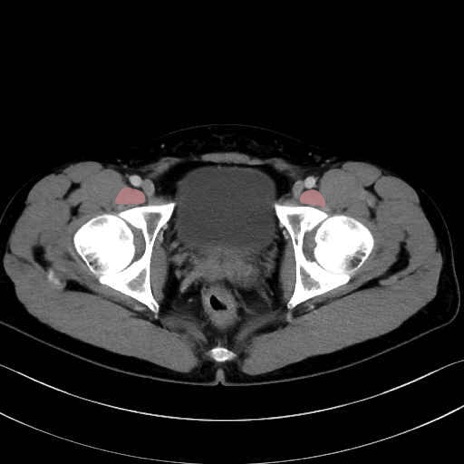

梨状筋 (Piriformis)

内閉鎖筋 (Obturator internus)